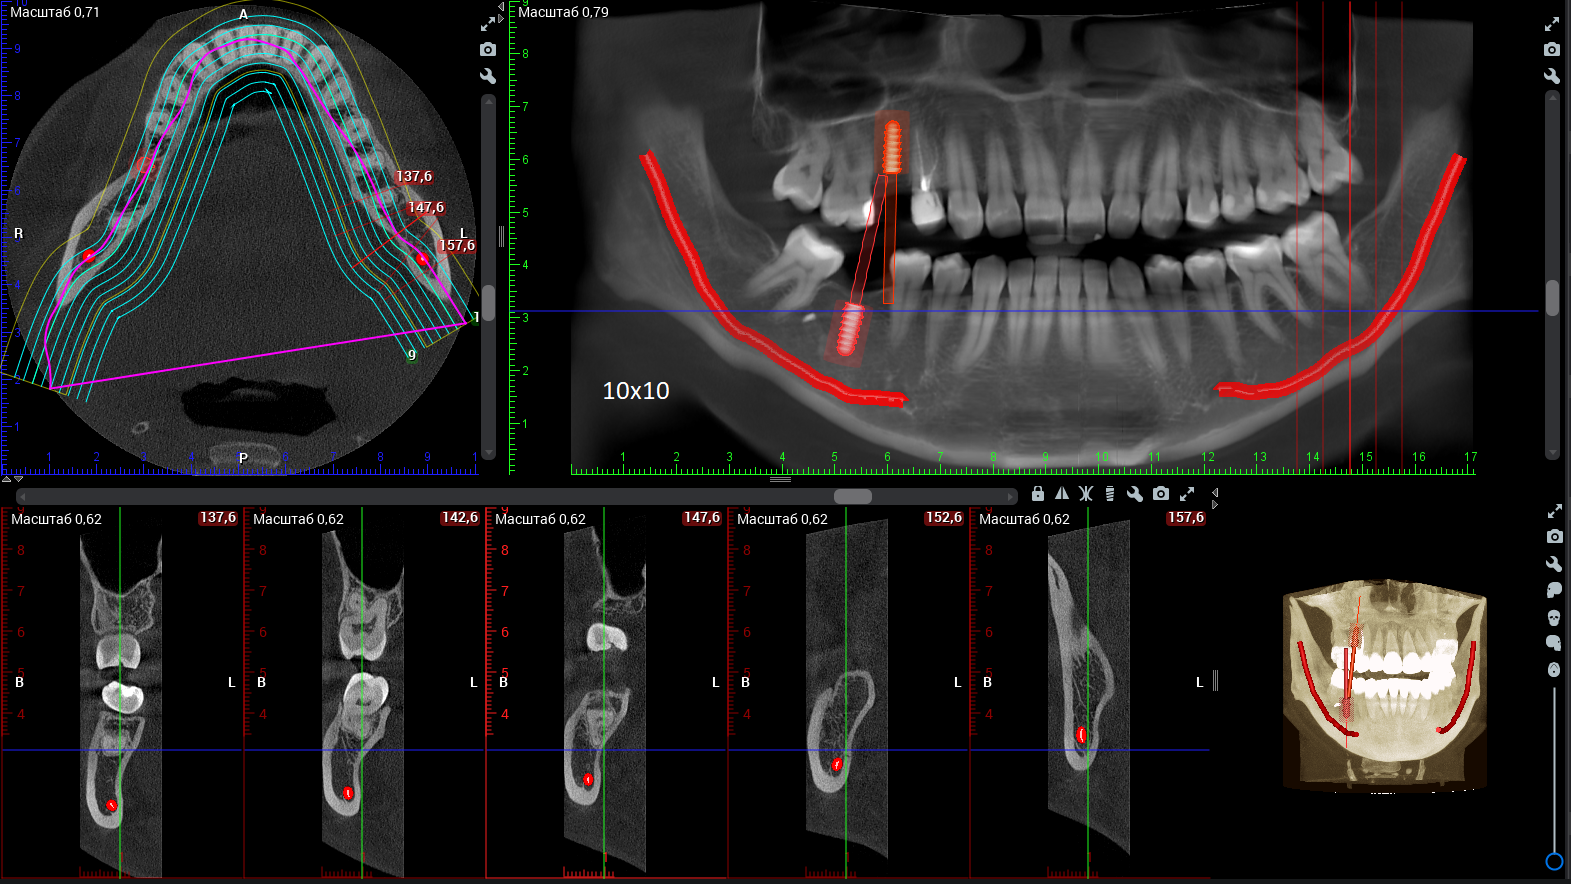

Стоматологические снимки

Мы делаем любые исследования зубов от трех зубов в высоком разрешении (например, для планирования перелечивания каналов) до исследования всей головы (зубы, придаточные пазухи). Имея большой набор разных исследований, доктор может направить вас именно на тот снимок, который ему необходим для решения конкретной задачи.

• Разметка для имплантации в области 1-го отсутствующего зуба

• Разметка в области двух челюстей перед имплантацией

• Разметка кортикальной пластинки в области одного зуба

• Описание в области одного зуба

• Описание двух челюстей